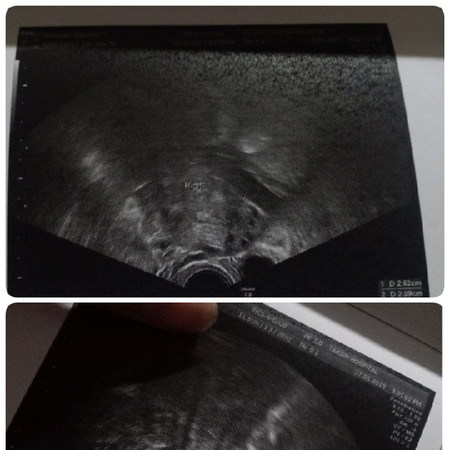

ถ้ามีถุงจะเป็นแบบนี้จ้า มีพื้นที่สีดำๆตรงกลางมดลูก